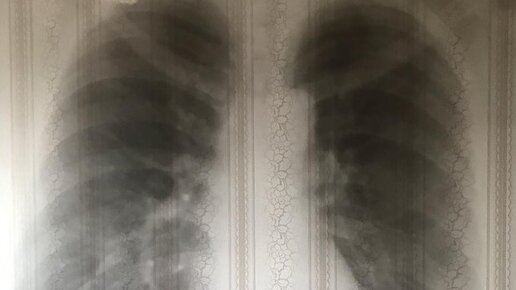

Что такое пневмония? Пневмония — распространенная респираторная инфекция, поражающая легкие. Воздушные мешки в одном или обоих легких воспаляются и могут заполняться жидкостью или гноем (гнойным материалом). Это может вызвать кашель с мокротой или гноем, лихорадку, озноб и затрудненное дыхание. Его могут вызывать различные организмы, такие как бактерии, вирусы и грибки. Пневмония может быть легкой или тяжелой, требующей медицинской помощи. В чем разница между вирусной и бактериальной пневмонией?...